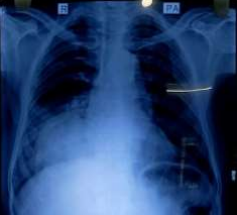

His first chest x-ray showed right lower lobe density surrounded by consolidation. Blood test showed neutrophilia and mild anemia. He was asked to do sputum for AFB and culture sensitivity, was prescribed oral antibiotics and asked for an Opd review after 10 days.

Fig 1: 1st Chest X-ray

Figure 1